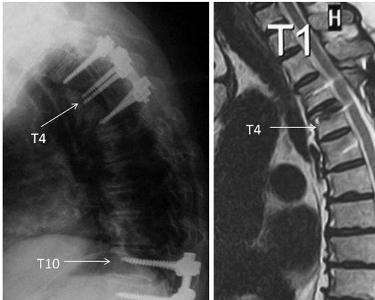

胸椎黄韧带骨化症多见于亚洲人,尤其是日本人常见,其发病率为5~25%。该病为一退变性疾病,50~70岁发病率高,有随年龄的增长发病率增高趋势,男性发病率高于女性,男女比例约为2:1。该病以下胸段多见,约占67%,上胸段6%,中胸段较少。